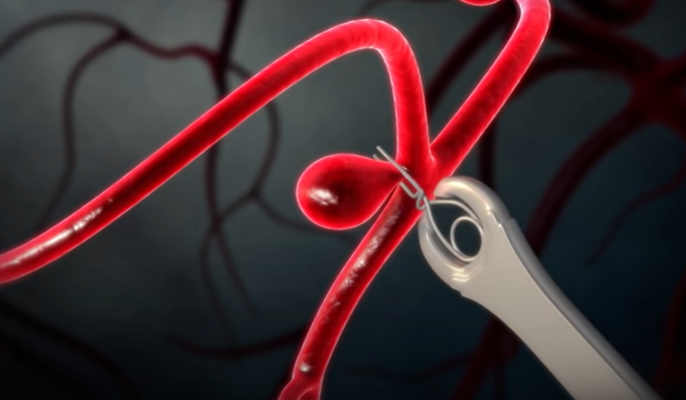

뇌동맥류 치료 : 클립 결찰술, 코일 색전술

직접 머리를 열어 뇌동맥류를 클립으로 묶어주는 경부 결찰술과

둘 다 뇌동맥류로 가는 혈류를 차단해 파열을 막아주는 효과가 있다.

대개 개두술, 경부 결찰술을 하는 뇌수술을 받으면 굉장히 위험하고 혈관 내 수술, 즉 코일 색전술은 안전하다 생각하는데 치료법의 결정은 동맥류의 모양에 큰 영향을 받는다. 경부(동맥류가 시작하는 목 부분)가 굉장히 좁고 동맥류 자체가 크면 코일 색전술을 하기 쉽다. 반대로 경부는 넓고 동맥류의 높이는 높지 않은데 위험한 위치에 있을 경우, 코일 색전술을 하면 동맥류가 불거진 부분에 코일일 지지할 곳이 없다. 이 경우 개두술을 하고 경부 결찰술을 시행하는 것이 훨씬 안전하고 효과적이다.